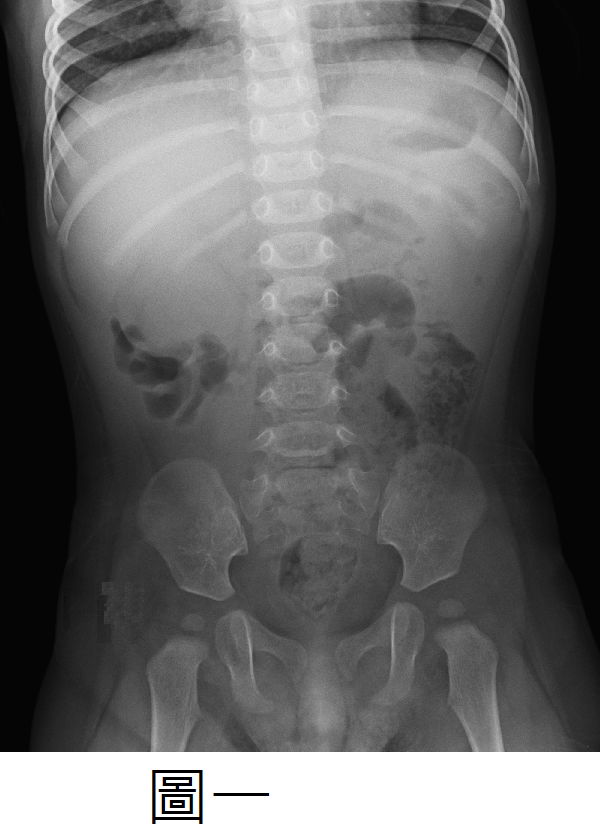

【110-1 醫學(四) 第12題】關於兒童急性闌尾炎(Acute appendicitis)之敘述,下列何者正確?

破題關鍵

掌握急性闌尾炎的典型臨床表現和診斷特徵。